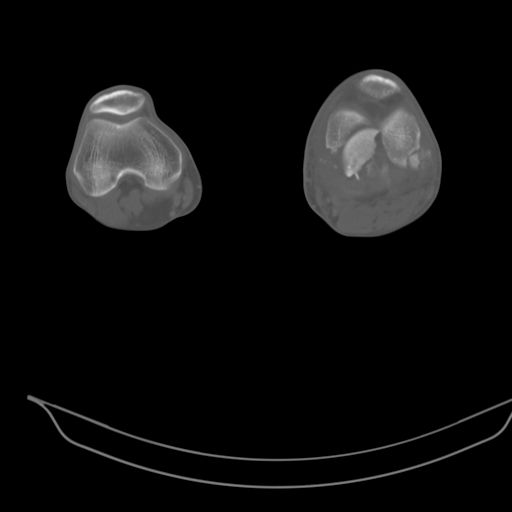

Качественные только исходные рентгенограммы (вышлю или завтра или в понедельник). Все последующие рентгенисследования были малоинформативны

(в т.ч. и последние снимки). КТ-исследование делалось 3 или 4 дня назад...

This is a coronal split in the femoral condyle and is a rare injury. Please see attachment for ORIF result

CT shows major bony fragments which are markedly rotated .With this amount of bony damage,you probably should attempt to get reasonably loooking knee with ORIF and thn if he needs a TKR due to pain a few years from now, then tleast you have something looking like a knee that you can replace rather than having to use revision knee for a primary TKR now. 4 weeks is not too long .what is the condition of soft tissues?

При внутрисуcтавных переломах трехмерные (3D) изображения, кроме красивого снимка, не дают полную информацию о состоянии отломков, самыми информативными являются корональные срезы на КТ и обычная длинная ренгенограмма конечности для сравнения оси конечности.

Фронтальные внутрисуставные переломы мыщельков бедра, так называемые Hoffa fracture, не частые, но встречающиеся переломы, в основном они связаны с травмой высокой энергией.